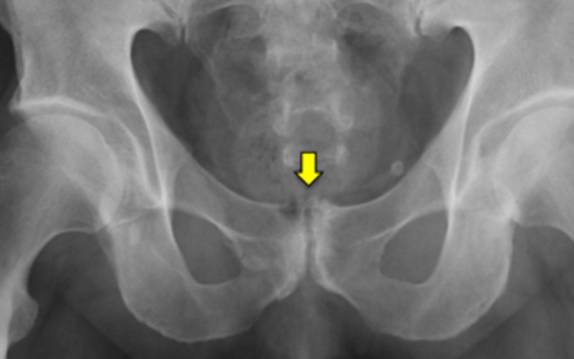

Possibili associazioni sono dolori a livello della sinfisi pubica (fig. 3) o dello psoas.

L’equipe della Chirurgia Ortopedica Ricostruttiva Tecniche Innovative ha messo a punto un percorso diagnostico-terapeutico dedicato ai pazienti affetti da coxalgia. L’iter prevede visita specialistica e l’integrazione con esami strumentali mirati (ecografia dinamica (fig. 5), radiografie con proiezioni specifiche, ricostruzioni tridimensionali TC (fig. 6), RMN ad alto campo, test con anestetico intra o extra-articolare).